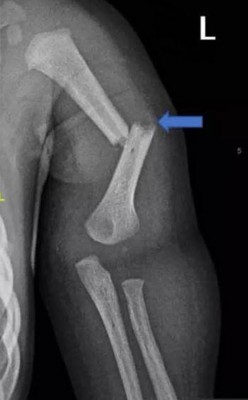

据英国《太阳报》报道,32岁男子建卓札克与22岁妻子柯宾丝卡,在2017年时把年仅4个月大的儿子送到医院,全身是伤。医师检查后认为状况有异,夫妻俩则直呼孩子是被边缘翘起来的地毯绊倒,但医师发现,孩子身上共有28处骨折,而且伤势相当严重,包括手臂、肋骨、膝盖、脚踝等几乎都是全断的状况。医师验伤认为,男婴遭到强大的外力冲击,因此报警处理,建卓札克和柯宾丝卡随后遭到警方逮捕。

检察官指控建卓札克与柯宾丝卡虐童,导致孩子至少有20多处严重骨折,来自严重外力撞击。报导也指出,建卓札克先前就有家暴官司,曾经对母亲动手,而这起虐童案,他在庭上毫无悔意。法官韩森表示,孩子没有先天疾病或不正常,但是身上却出现许多异常伤势,很明显地非来自意外伤害,是遭到父母恶意造成,最后判处建卓札克8年徒刑,且必须服完3分之2刑期才有机会申请假释。